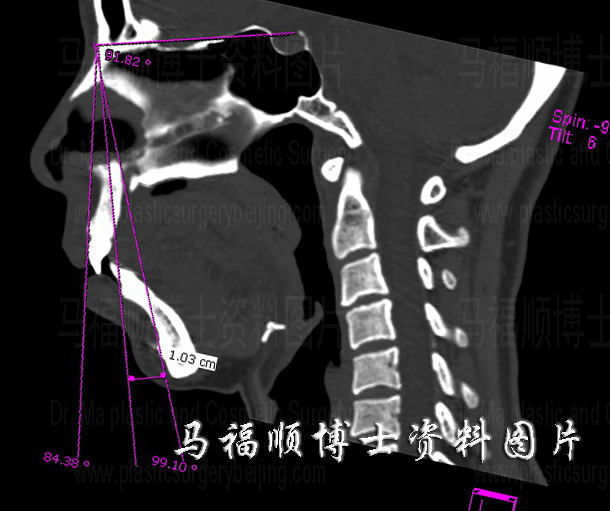

Saggital section CT shows the protrusion upper and lower jaw forming a sharp contrast with the retrograded chin bone.

As previously described this girl underwent three separate surgeries. The first surgery, bimaxillary correction surgery changed her facial contour mostly because bimaxillary protrusion was the biggest problem on her face. Showing on the right side CT image her upper and lower jaw bone and incisors protruded to the front in a great scale. Once this protruding problem is corrected her facial appearance is improved fundamentally. The pre surgery profile photo and the CT image also show that she had a small chin, the difference between angle SNA and angle SND reaches 15 degrees (normally around 6 degrees), which made the protrusion of mouth even more stand out. Though an “H” osteotomy had been used to move the chin forward at the same time of setting back the lower teeth by rotating the freed bone piece, the scale of forwarding chin movement is still not enough to correct the micorgnathia. Another surgery of Forward Sliding Genioplasty also know as Horizontal Osteotomy Chin Sliding Surgery was performed to slid her chin forward for 1 CM. Then she got the satisfactory final result as showing in the post surgical photos.

For those who suffer from bimaxillary protrusion the correction surgery is undoubtedly a high reward investment. Choosing the right indication and calculating the right amount of bone movement are key for a successful correction. An under scaled set back of bone may not completely correct the protrusion, an over scaled set back may make the candidate in an aging facial appearance. Thanks to the modern CT technology surgeons can calculate the scale of protrusion acutely and analyze the relationship between the upper and lower jaw bones, and also their relationship to the other facial bones prior to the operation. This can make the bone movement very accurate and the operating time shorter.